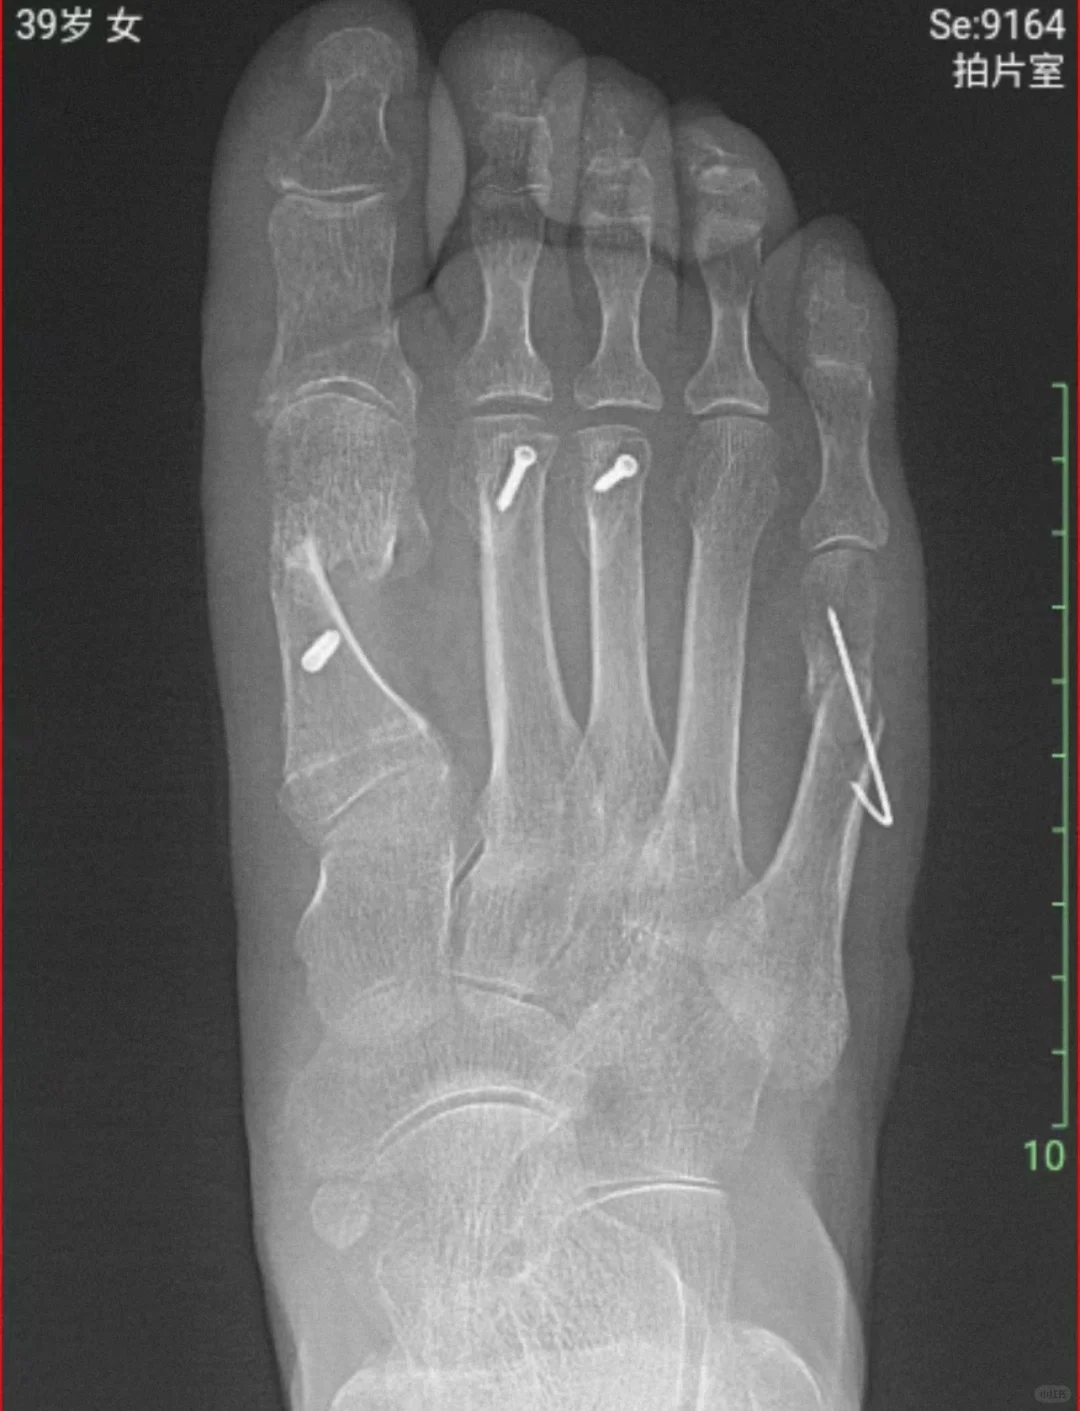

拇外翻术后X片